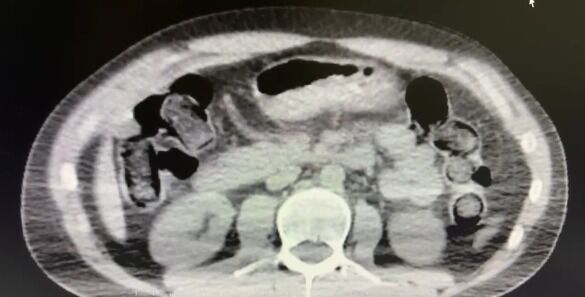

Ekipler, S.B. ve O.R. isimli şüphelilerin “yutma yöntemi” ile kente uyuşturucu madde getireceği bilgisi üzerine harekete geçti. Şüphelilerin konutlarında ve kullandıkları araçlarda yapılan aramalarda

• 101 kapsül halinde 722 gram metamfetamin,